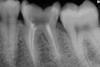

Julyetta Опубликовано 2 апреля, 2011 Поделиться Опубликовано 2 апреля, 2011 на мой взгляд,каналы пролечены довольно неплохо,хотя качество снимка не позволяет 100%качественно оценить ситуацию,по нему пропущенных каналов не обнаружила,а вот боли уж очень напоминают боли из-за зубодесневого кармана,по снимку они имеются,порой десневая боль не менее неприятна,чем зубная) Ссылка на комментарий

mdkvrn Опубликовано 3 апреля, 2011 Поделиться Опубликовано 3 апреля, 2011 Каналы вроде залечены хорошо, а вот воспаление на дистальном корне есть, зачем же вы 2 недели себя мучали, сразу бы пришли и не было бы проблем... Ссылка на комментарий

stom_baku Опубликовано 3 апреля, 2011 Поделиться Опубликовано 3 апреля, 2011 по снимку видно что в дистальном канале паста(или гуттаперча) выходить из апекса, вполне вероятно что причиной боли является этот факт. Ссылка на комментарий

artist.doc Опубликовано 3 апреля, 2011 Поделиться Опубликовано 3 апреля, 2011 Здравствуйте. У меня сильно болел зуб. Я держалась на таблетках где-то 2 недели. Потом все же пошла к врачу. Он удалил мне нервы, заполнил каналы. Прошло 2 дня а зуб у меня все еще сильно болит и чешется. Я даже зубы смыкать не могу, сильная боль возникает. Врач говорил что некоторое время будет боль при нажатии на зуб. Но об острых болях и о зуде в зубе ничего не сказал...я все еще принимаю обезболивающие. Подскажите пожалуйста в чем может быть проблема? Вот снимок зуба. После пломбировки каналов некоторыми пломбировочными материалами при выведении материала за верхушку корня зуба бывает сопровождение болей и зуд в зубе. Может продлиться около недели, нужно добавить противовоспалительный препарат к обезболивающему, со временем боль должна уйти и в 6 зубе чаще всего 4 канала. Ссылка на комментарий